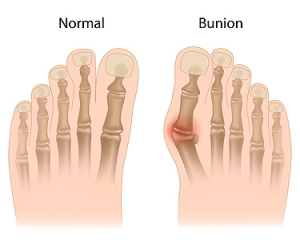

Bunions, a prevalent foot condition, can cast a shadow on even the most graceful strides. A bunion, or hallux valgus, emerges when the joint at the base of the big toe shifts out of alignment, causing the toe to lean toward the other toes. The reasons why bunions may develop can vary, often stemming from genetic predisposition. Additionally, wearing ill-fitting footwear that squeezes the toes, or conditions that impact foot mechanics may lead to getting a bunion. The symptoms manifest as a bony bump at the base of the big toe, accompanied by pain, swelling, and redness. As the condition progresses, the affected toe may cross over or under the adjacent toe, causing discomfort and it can be difficult to find comfortable shoes. Recognizing the definition, causes, and symptoms of bunions is crucial in seeking the correct treatment. If you have a bunion, it is suggested that you consult with a podiatrist who can guide you toward the relief and treatment options that are best for you.

What Is a Bunion?

A bunion is formed of swollen tissue or an enlargement of boney growth, usually located at the base joint of the toe that connects to the foot. The swelling occurs due to the bones in the big toe shifting inward, which impacts the other toes of the foot. This causes the area around the base of the big toe to become inflamed and painful.

Bunions

A bunion is a bump that forms at the base of the big toe. Bunions form when the big toe pushes against the next toe, which forces the big toe joint to get bigger and stick out. As a result, the skin over the bunion may start to appear red and it may feel sore.

The most obvious way to tell if you have a bunion is to look for the big toe pushing up against the toe next to it. Bunions produce a large protrusion at the base of the big toe and may or may not cause pain. Other symptoms are redness, swelling, and restricted movement of the big toe if you have arthritis.